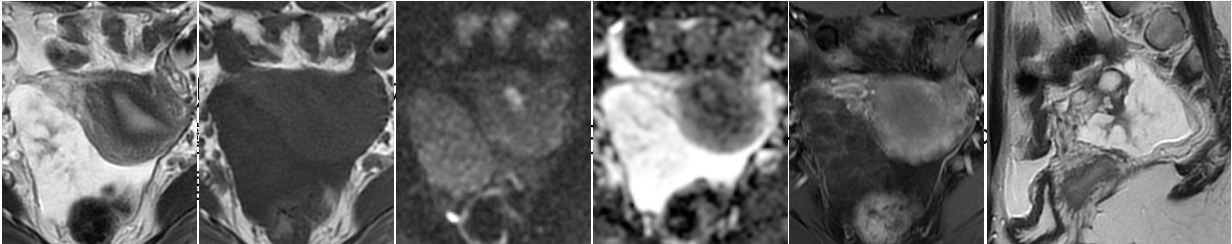

【外向性発育を示すSBT ②】

• MRI所見

藤本真理子ら.三菱京都病院医学総合雑誌 22: 26-29, 2015.

【外向性発育を示すSBT ①】

Sahin H, et al. Br J Radiol. 2021;94:20210116.

Tsuboyama T, et al. RadioGraphics. 2022;42:2095–2111

【外向性発育を示すSBT ③】